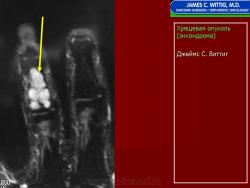

Энхондрома (син.: хондрома, центральная хондрома) — доброкачественная хрящевая опухоль, расположенная в костномозговом канале (интрамедуллярно). Встречается в 10 % случаев от общего числа доброкачественных опухолей костей. Считается, что она возникает из эктопически расположенных островков хряща, отщепившегося от пластинки роста на ранних этапах онтогенеза. В ряде случаев опухоль остается бессимптомной и обнаруживается случайно при рентгенологическом исследовании. В других случаях возникают боль и припухлость. Обычно болезненными становятся все энхондромы фаланг. Наиболее частая локализация: фаланги, главным образом, пальцев кистей, проксимальный конец плечевой кости, проксимальный или дистальный концы бедренной кости. При рентгенологическом исследовании в энхондроме определяются просветления с участками минерализации. Тень кости становится более широкой, кортикальный слой сохраняет целостность, но истончается. В редких случаях энхондрома имеет вид эксцентрически растущего экзофитного новообразования. Макроскопически опухоль представляет собой голубовато-белую полупрозрачную хрящевую ткань, в которую вкраплены желтоватые участки обызвествления. Опухоль состоит из отдельных хрящевых узелков, диаметр которых варьирует в пределах 1 см.

Рентгенологическая картина хондромы представляет четко очерченный опухолевый узел. Очаги минерализации в хондромах выглядят достаточно характерно и представлены очаговыми, глыбчатыми или кольцевидными , арочными отложениями извести. Полного разрушения кортикального слоя трубчатой кости с выходом опухолевых масс в мягкие ткани не наблюдается.